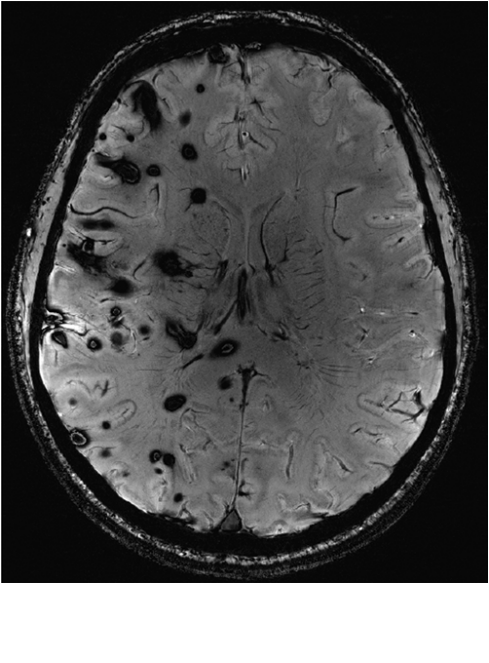

在7-TSWI时,CCM的总数为681,平均数为22.440.0(范围2-153)。17例出现多灶分布。在11例患者中发现CCMs与典型的DVA相关。未检测到与局部静脉异常相关的其他CCM。在16例患者中,至少有1例CCM超过10mm。根据Zabramski分类,19例患者(33例CCM)中发现了Ia/b型,14例患者(30例CCM),2例患者(4例CCM中)发现了III型,1例患者发现了IV型。613个病灶仅在SWI上可见小信号消除。病灶内或病灶外大出血(>10mm)9例。发育性静脉异常显示2.51.9(范围1-7)收集静脉。在9例DVAs中证实了狭窄,9例DVA中证实了集合静脉的成角走行。8个被归类为大型,3个为中型。进一步的细节如表4所示。根据MRI标准,患者被分为两组:(多)无相关DVA的病灶分布(分散型;图1)和相关DVA(簇型;图2)。有关详细信息,请参见表2和表3。图3中提供了模式示意图。在1.5-TSWI(n=25)下,检测到的CCM总数低于7-TMRI(平均33.241.3对39.849.2个病灶)。6例患者中检出的病变较少。两种成像方式的DVA检出率相似。

在本研究中,多发性CCM的MRI模式在疑似散发性(阴性基因筛查)和家族性(阳性基因筛查)疾病形式之间明显不同。疑似散发性CCM的疾病分布仅限于大脑的1或2个区域,多灶性DVA患者除外(病例1和11;表2)。在Confrmed家族性疾病中,CCM分布在大脑的多个区域,除了2例仅出现少数病变(分别为2和4个CCM)(病例2和7;表3)。因此,总的来说,与家族性病例相比,散发性病例中发现的病变较少。然而,一半患有家族性疾病的患者显示病变负荷<10CCMs。较重要的是,CCM位于集合静脉引流区的典型DVA与全部病例的阴性基因筛查相关,表明为散发性疾病。在全部Confrmed家族病例中均未发现相关的典型DVA或局部静脉异常。这些差异具有统计学意义。两组之间显示急性出血的病变数量(Ia和Ib型与II、III和IV型相比)或病变大小没有差异。基于脑内分布的重复模式以及与DVA的关联/不关联,我们建议将模式命名为集群型(散发型)和分散型(家族型)。